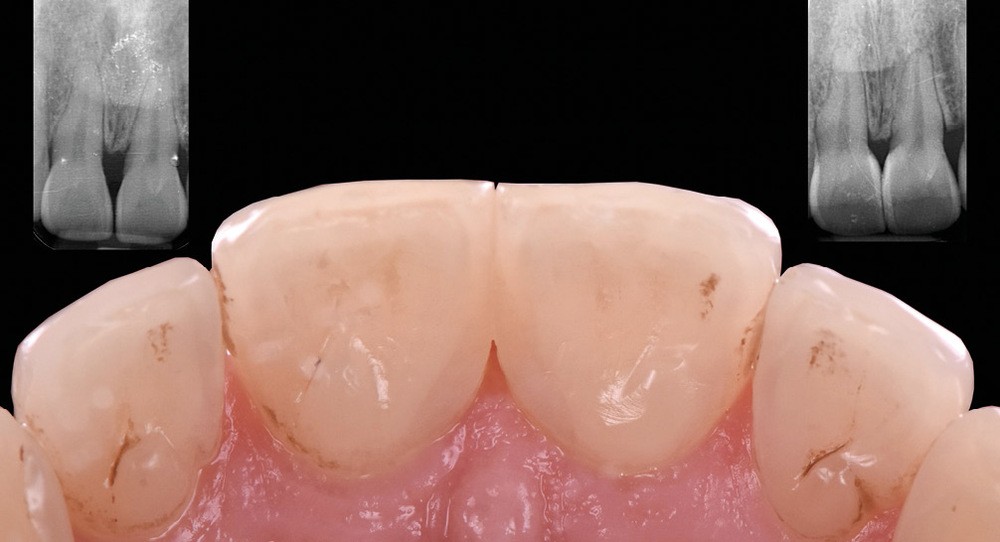

Les triangles noirs

Ils correspondent à une perte de papille interdentaire et sont principalement observés :

– lorsque la distance point de contact/crête osseuse est supérieure à 5 mm ;

– chez des patients présentant une atteinte parodontale avec une perte osseuse associée à une récession horizontale ;

– pour des dents le plus souvent de forme triangulaires ;

– en post-traitement orthodontique.